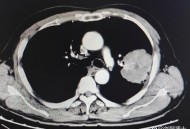

>> 顶尖肺癌专家患肺癌

网络资讯顶尖肺癌专家患肺癌,顶尖肺癌专家患肺癌的几率大家好,今天小编关注到一个比较有意思的话题,就是关于顶尖肺癌专家患肺癌的问题,于是小编就整理了1个相关介绍顶尖肺癌专家患肺癌的解答,让我们一起看看吧。著名相声演...发布时间:2025年09月29日立即查看 -

网络资讯顶尖肺癌专家患肺癌,某著名作家经常作肺癌检查,为何还未早期发现呢?医院要担责吗?大家好,今天小编关注到一个比较有意思的话题,就是关于顶尖肺癌专家患肺癌的问题,于是小编就整理了1个相关介绍顶尖肺癌专家患肺癌的解答,让我们一起看看吧。某著名作家...发布时间:2025年09月28日立即查看